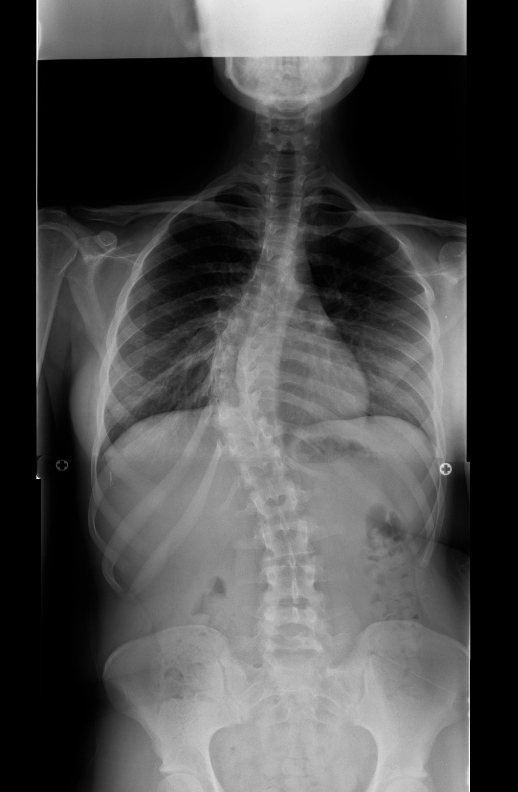

| Pre-op | Post-op |